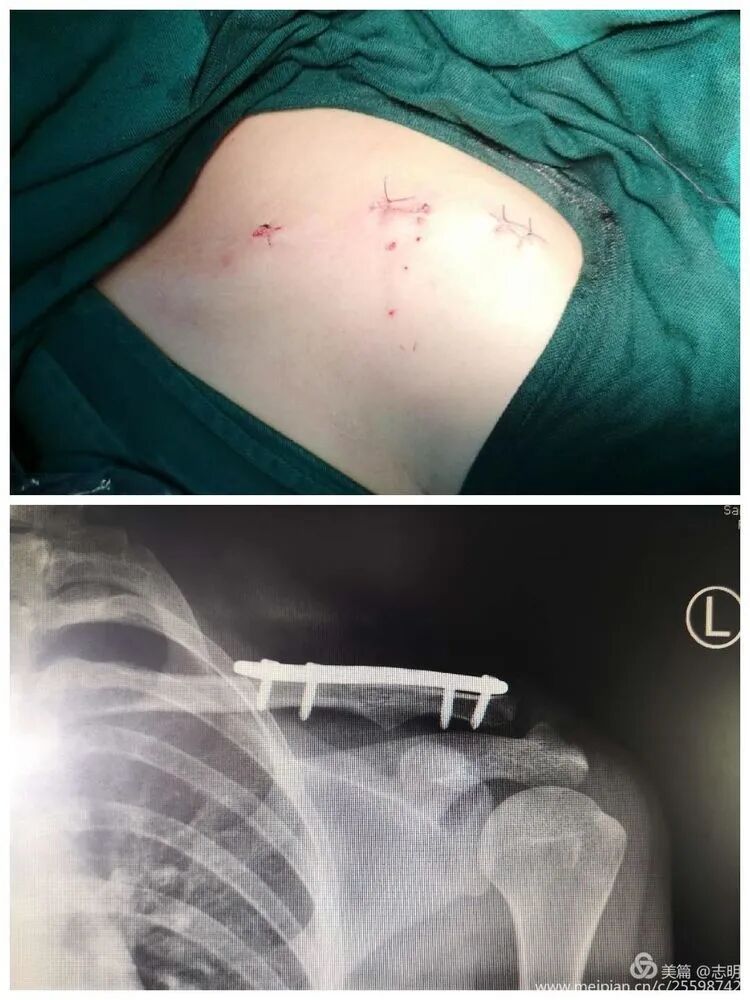

(Post-fixation X-ray showing the plate and screws in place).(Another post-fixation X-ray).

- Close the small skin incisions in a layered fashion. Ensure meticulous hemostasis to prevent hematoma formation, which can compromise the cosmetic outcome and increase infection risk.

- The primary cosmetic advantage of MIPO derives from these minimal incisions, resulting in significantly less visible scarring.

(Clinical image of small, well-healed MIPO incisions).(Another clinical view of minimal scarring).(Close-up of a small post-operative incision).(Clinical view of small post-operative incisions).(Clinical image demonstrating good range of motion post-operatively).